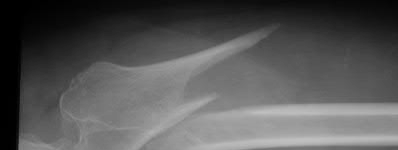

Figure A shows a radiograph of a 19-year-old male with an isolated shotgun injury. On physical examination, he has a 3 cm wound over the posterolateral aspect of his arm. In addition, he has weakness with wrist and finger extension, but no sensory deficits. The patient has received tetanus prophylaxis and antibiotics in the emergency department. What would be the next best steps in treatment?

This patient has sustained a shotgun blast to the midshaft humerus. The next best step would be irrigation and debridement, and external fixation of the fracture.

Shotgun injuries are typically treated as open fractures, whereas low-energy gunshot wounds are treated as closed fractures. The initial operative treatment of shotgun wounds should include irrigation and debridement and stabilization with external fixation. The goal of treatment is to stabilize the severe soft-tissue injury and bone loss, as well as to aggressively debride devitalized tissue and gross contamination.

Figure A shows a high velocity shotgun fracture to the left humerus with retained buck fragments. Illustration A shows a similar injury stabilized with external fixation.